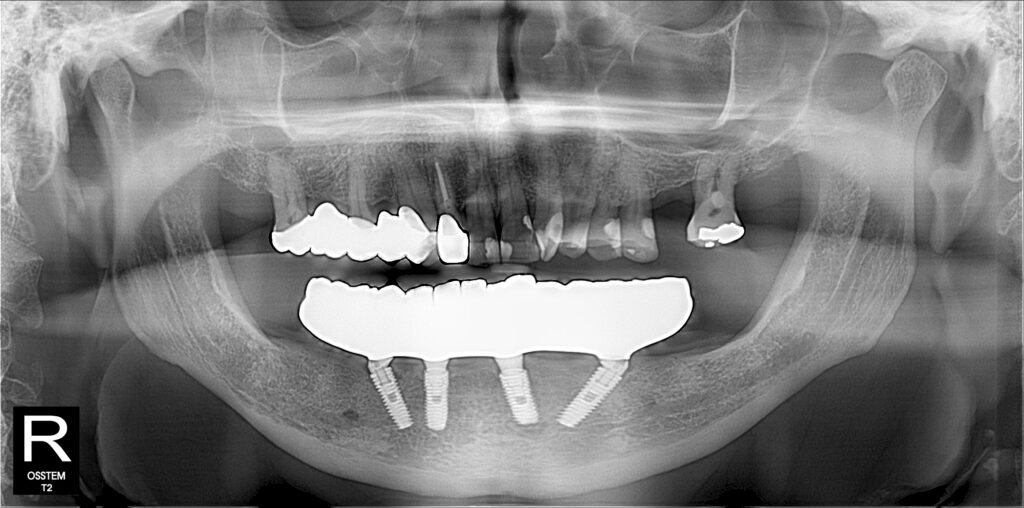

A selection of full arch fixed implant bridge patients after 5 years of wear

Oral Surgeons – Dr Han Choi, Dr Sam Goldsmith, Dr Rajiv Rajpal NSOMS

Prosthodontist – Dr Alan Payne NSOMS/Northland Prosthodontics

Dental technicians – Hosaka Takashi, DT Denture Design, Auckland, CJ Park, Project Dentistry, Auckland and Osteon Medical, Melbourne, Australia.